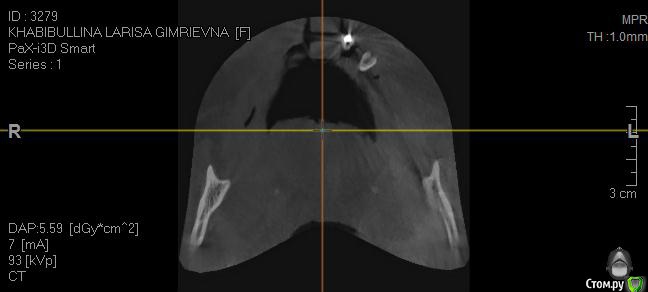

Здравствуйте. 59 лет. 9 лет на обеих челюстях стояли бюгельные протезы на замках.

1.        Верхняя челюсть – полная адентия (имеется один корень клык)

2.        Нижняя челюсть – протез просел – в коррекции отказано, (с левой стороны протез держится на отдельно стоящем подвижном зубе, т.к. распалось соединение с зубным рядом.)

- Нижняя челюсть выдвинулась в перед (возрастной мезиальный прикус)

- Нижняя челюсть гипермобильна , дисфункция ВНЧС, хрустит прикус прогенически,  (диагноз ЧЯХ (в лечение отказан) Рот открывается рывком (безболезненно)

3. Съёмный протез на верхнюю челюсть сделан некорректно, без учета прикуса (сточена на половину правая часть искуса), верхний протез выдвинут вперед (получился дистальный глубокий прикус), напряжение в нижней челюсти.

2. Достаточно ли кости для проведение имплантации? Нужна ли ринопластика?